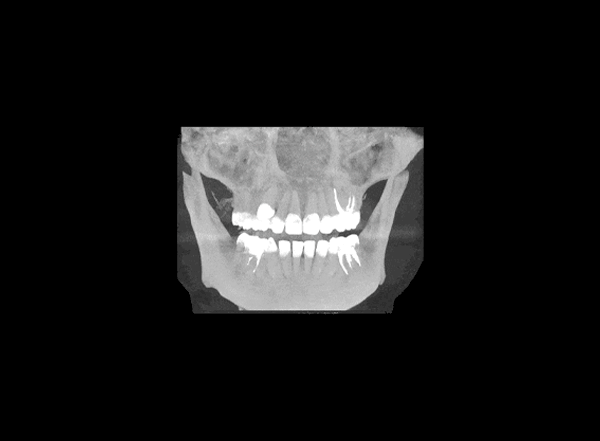

Первый визит — это осмотр и 3D-диагностика (КТ).

Врач оценивает:

• состояние кости,

• состояние дёсен,

• общее положение челюсти и прикуса.

Если всё в порядке, можно планировать установку. Если есть воспаление, кариес или пародонтоз — их нужно вылечить до имплантации.